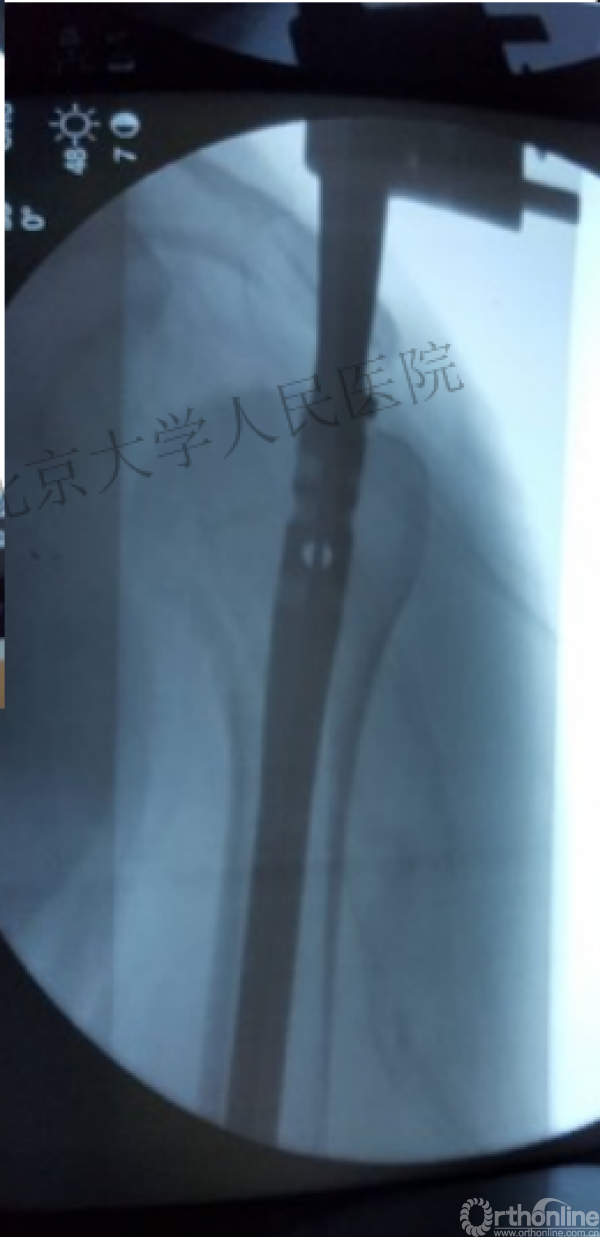

术中片